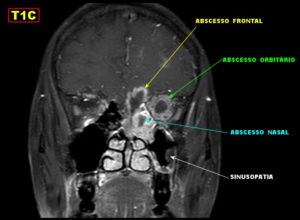

Единственными методами, которые наверняка могут определить сфеноидит, являются компьютерная томография (КТ) или магнитно-резонансная томография (МРТ) –